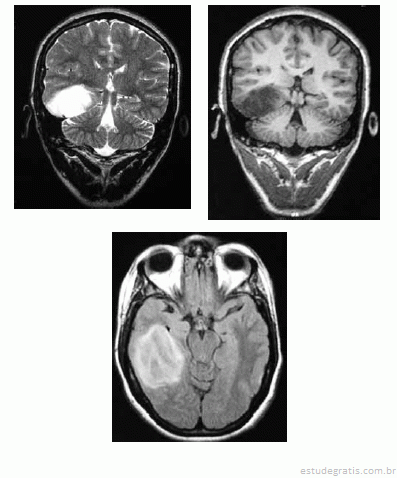

Uma mulher de 36 anos de idade foi encaminhada ao ambulatório de neurologia por dificuldade no controle das crises epilépticas. Ela referiu ter tido uma convulsão febril aos 36 meses e ter passado a ter crises em que ficava “fora do ar” aos 11 anos. Ela recebeu o diagnóstico de epilepsia generalizada do tipo ausência e foi-lhe prescrito fenobarbital. Desde então, já fez uso de primidona, ácido valpróico e diazepam, em monoterapia e associados ao fenobarbital, sem sucesso. No exame, a paciente apresentava um comprometimento da memória recente e aparentava ter um sutil deficit dos campos visuais e Babinski à esquerda. Apesar de trazer um EEG normal, foi solicitada RNM de encéfalo, que é reproduzida abaixo.

Com base nas alterações do exame neurológico e da RNM, é correto afirmar que o diagnóstico dado à paciente foi incorreto.Comentários